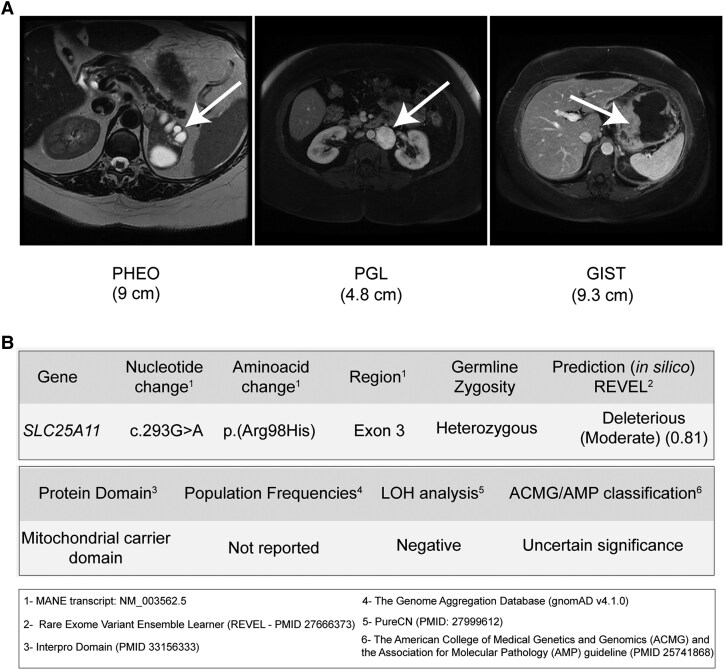

Methods: Histological, genetic, and functional analyses were conducted in a 59-year-old female with CSS (9 cm left pheochromocytoma, 4.8 cm paraganglioma, and 9.3 cm GIST). Whole-exome sequencing (WES) of germline DNA paired with tumor DNA was performed.

Results: WES identified a rare heterozygous germline variant (c.293G>A/p.Arg98His) in the mitochondrial 2-oxoglutarate/malate carrier gene (SLC25A11). This variant, located in a highly conserved residue of the SLC25A11 mitochondrial carrier domain, is predicted to be deleterious in silico (REVEL score = 0.81). WES of pheochromocytoma, paraganglioma, and GIST did not reveal somatic pathogenic variants in genes previously associated with these tumors. A significant reduction in SLC25A11 expression was observed in the tumors of this patient with the SLC25A11 c.293G>A variant (0.69 ± 0.003) compared to tumors from cluster 1 (1.39 ± 0.45; P = 0.0229) and cluster 2 (1.79 ± 0.71; P = .0154). Consistent with the mRNA findings, SLC25A11 protein levels were markedly reduced in the pheochromocytoma and paraganglioma compared to other tumors. Negative staining for 5-hydroxymethylcytosine in all 3 tumors suggests a DNA hypermethylation profile characteristic of cluster 1A, despite normal SDHB expression levels. However, genome-wide copy number variation analysis did not reveal any loss of heterozygosity at the SLC25A11 locus.